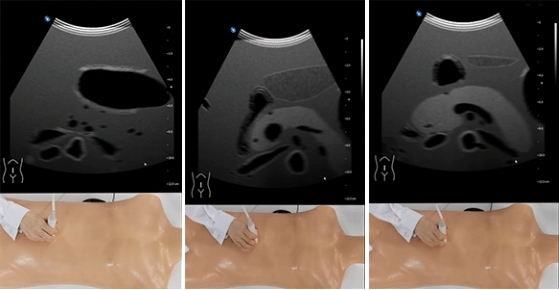

超声模拟实训系统 单机版(女)

超声模拟实训系统 单机版(女)

超声模拟实训系统 单机版(男)

超声模拟实训系统 单机版(男)

超声模拟实训系统 学生机

超声模拟实训系统 学生机

超声模拟实训系统 教师机

超声模拟实训系统 教师机